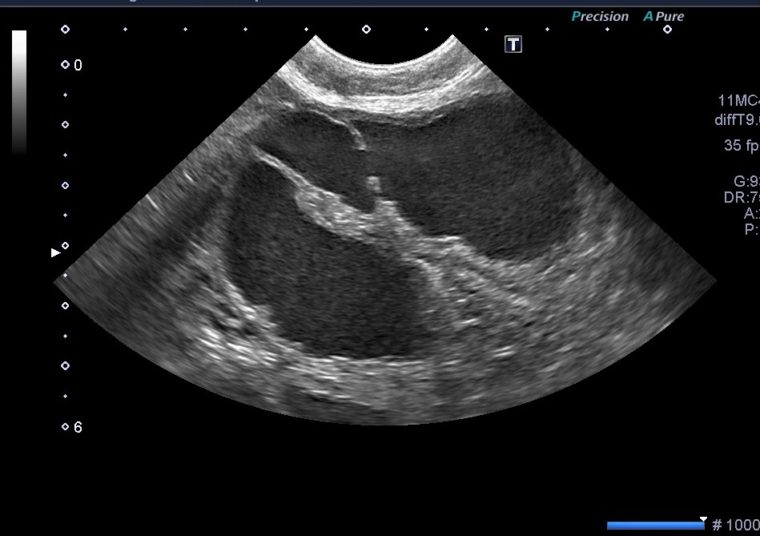

動物病院では症状、血液検査、レントゲン検査、超音波画像診断検査などにより子宮蓄膿症をほぼ正確に発見診断できます。